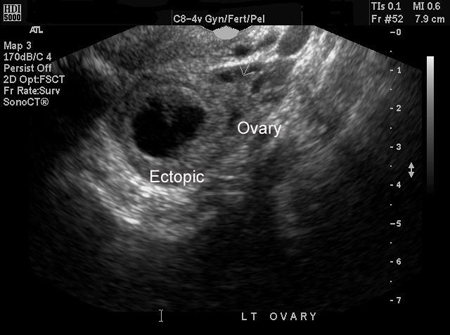

An ectopic pregnancy can be definitively diagnosed via ultrasound when a gestational sac with a yolk sac, or embryo, or both, is noted in the adnexa.[47] Not all ectopic pregnancies can be visualised on ultrasound; however, with increasingly high-resolution ultrasound and expert sonography, studies have shown that TVUS is both highly sensitive and specific in the diagnosis of ectopic pregnancy. However, there remains a significant proportion of cases (between 5% and 42%) where neither an intrauterine nor an ectopic pregnancy can be visualised on ultrasound. In these cases, the descriptive term pregnancy of unknown location (PUL) is used.[48][49][Figure caption and citation for the preceding image starts]: Ultrasound image of ectopic pregnancyFrom the collection of Dr Melissa Fries; used with permission [Citation ends].

[Figure caption and citation for the preceding image starts]: Ultrasound image of ectopic pregnancyFrom the collection of Dr Melissa Fries; used with permission [Citation ends].